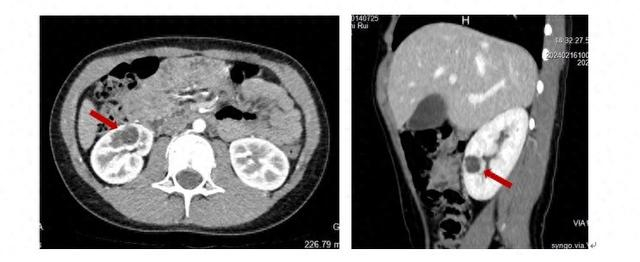

新华医院泌尿外科崔心刚教授在接诊后通过详细的检查发现磊磊的右肾肿块为多房囊性肿瘤伴分隔,随即安排磊磊入院并行微创保肾手术

由于磊磊的右肾肿块为完全内生性,在肾脏表面无法直接分辨出肿瘤的具体位置,想要尽可能少的切除正常肾组织,需精确定位肿瘤的边界。崔心刚教授在为磊磊进行达芬奇机器人保肾手术时,通过机器人下超声准确探查出肿瘤的边界,快速切除了肿瘤并缝合创面,肾动脉阻断时间不足10分钟,很好的保护了患肾的功能。